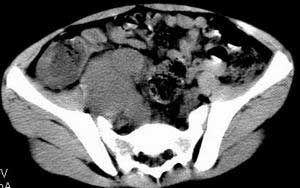

| 患者,男,9岁,因右下腹包块入院,血象不高,不规则发热,常超40度。 平扫: ![]() ![]() ![]() ![]() ![]() ![]() ![]() ![]() ![]() ![]() ![]() ![]() ![]() ![]() ![]() ![]() ![]() ![]() 增强: ![]() ![]() ![]() ![]() ![]() ![]() ![]() ![]() ![]() ![]() ![]() ![]() ![]() ![]() jiajie发言:骶椎右前区不规则软组织肿块,边缘光整,密度均匀,增强后均匀强化,右腹股沟区可见肿大淋巴结,临床有时发热,考虑淋巴瘤,儿童盆腔肿瘤应与神经母细胞瘤和横纹肌肉瘤鉴别。 longzhanghui发言:印象:盆腔右后壁不规则软组织肿块,并向前延伸.似为多个肿块融合,呈中等强化.初步考虑淋巴瘤. 听蝉观竹发言:右侧髂内、外组淋巴结肿大,从其形态和融合的情况看,同意大家意见-----考虑恶性病变,但是9岁男孩还要注意检查睾丸情况,有无隐睾? 常常类似情况是隐睾发生精原细胞瘤淋巴结转移,这个病例也要注意这一点!!! 广东凌发言:大家好,在这里我想说一下个人观点,我建议上传图片的同志能否辛苦一点就是把病史和图片都上传完整一点,比如这个病人的腹膜窗,并且这个病人的肠道的准备也是不怎么好,就从现有的质料看:病灶属于淋巴结肿大当无大的争议,有融合趋势,其内无坏死,边缘强化为主,故考虑:淋巴瘤!建议用腹膜窗看一下和肠道的关系! 阿圣发言:病灶属于淋巴结肿大当无大的争议,有融合趋势,其内无坏死,边缘强化为主,故考虑:淋巴瘤 结果是:淋巴瘤 病例来源:ct762。由宁静致远发布: http://www.radinet.com.cn/forum_view.asp?forum_id=4&view_id=2182 |